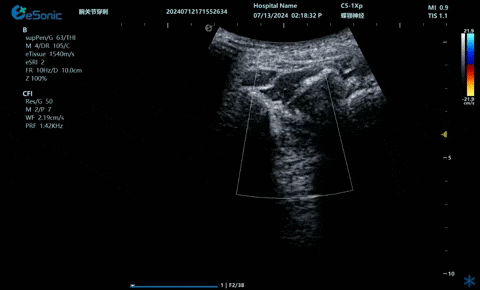

02

超声引导下肋间神经阻滞切面

疼痛康复领域中的肌骨超声应用,旨在实现对肌肉、肌腱、韧带、关节、神经、血管、筋膜、滑膜、滑囊、骨膜等组织结构的精确诊断评估。由于超声高频探头对上述机体组织的细微结构具有优异的分辨率,因此能够更为明确地评估这些组织的损伤和炎症状态。同时,超声设备的实时动态评估能力,使得对运动中的相关疾患也能进行准确的评估,这是其他诊断设备所不具备的优势。在康复治疗过程中,肌骨超声还用于介入穿刺治疗,如外周神经阻滞(PNB)、小关节注射、肌筋膜松解术、封闭、小针刀、冲击波治疗等。在超声引导下,这些治疗操作实现了可视化,从而真正意义上实现了精准医疗。以PNB为例,作为一种局部用药方式,其对患者全身干扰小,药物副作用少,且费用较低,因此仍然是临床治疗疼痛的主要方式之一近年来,超声技术在临床康复领域的应用日益凸显其优势。相较于传统的盲穿技术,超声引导下的PNB能够直观显示穿刺和注药过程,无需患者表达异感,避免了反复穿刺给患者带来的痛苦。这种技术显著提高了外周神经阻滞、静脉穿刺的成功率、精确性和安全性,同时减少了不良反应和并发症的发生,为患者带来了福音也相信在不久的将来,eHertz系列产品将会在全球医疗市场上掀起一场技术革新的风暴,让更多的人受益于我国医疗技术的进步。